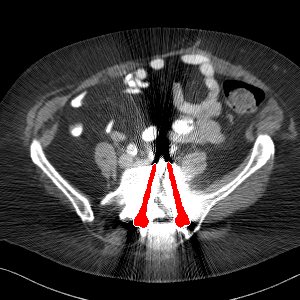

Visual comparison. As shown in Fig. 5, metallic implants such as spinal rods and hip prosthesis cause severe streaky artifacts and metal shadows, which obscure bone structures around them. cGan-CT cannot recover image intensity correctly for both cases. Sinogram domain or dual-domain methods perform much better than cGan-CT. LI, NMAR, and CNNMAR introduce strong secondary artifacts and distort the whole images. In NMAR images, there are fake bone structures around the metals, which is related to segmentation error in the prior image from strong metal artifacts. The segmentation error is also visible in NMAR sinogram. CNNMAR cannot restore the correct bone structures between rods in case 1. The tissues around the metals are over-smoothed in DuDoNet because LI sinogram and image are used as inputs, and the missing information cannot be inferred later. Our model retains more structural information than DuDoNet and generates anatomically more faithful artifact-reduced images.

Visual comparison. Fig. 7 shows two clinical CT images with metal artifacts. Case 1 is with moderate metal artifacts. cGan-CT does not suppress the artifacts completely and generates some fake details. LI, NMAR, CNN-MAR remove all the artifacts but introduce new streak artifacts, which is caused by the discontinuity in the corrected sinogram. DuDoNet outputs over-smoothed sinogram, which leads to blurred tissues close to the metal implants, such as muscle and bone. Only our model can provide realistic enhanced sinogram and remove the artifacts while retaining the structure of nearby tissues. Case 2 is very challenging as the rods bring strong metal shadows and bright artifacts around the vertebra. cGan-CT recovers the shape of vertebra but changes the overall image intensity. Other sinogram inpainting methods fail as the soft tissue and bone near the rods are heavily distorted. Our model removes part of the dark bands and reproduces correct anatomical structures around the rods.